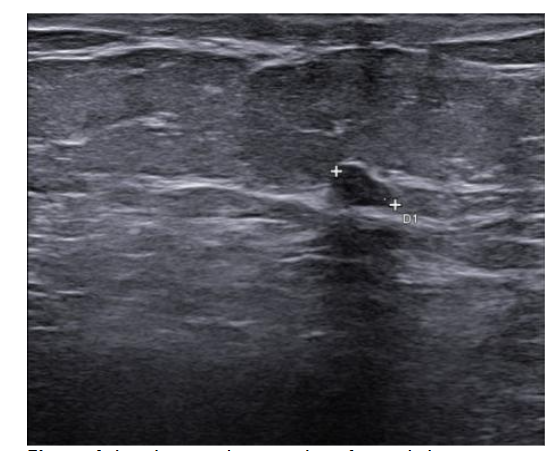

We stopped azacitidine and we promptly biopsied the nodule with a diagnosis of breast infiltration by AML blasts carrying the NPM1 mutation. CT scan and PET of chest, neck and abdomen were negative, and BM evaluation showed 1% blasts, with NPM1 0.044. The FLT3-ITD mutation resulted positive on breast cells while negative on medullary blasts. Thus, concluding for extramedullary relapse of AML FLT3-ITD mutated, we decided to start gilteritinib as single agent, at a dose of 120 mg daily. After 30 days, mammary ultrasound showed a reduction in diameter of the nodule.

In 4 months, the lesion has completely disappeared. The PET scan performed after 5 months of treatment was persistently negative and confirmed the absence of other uptakes. BM re-evaluation showed no blasts, with NPM1 0.006. Today, after 44 months of treatment, our patient is still in CR without signs of clinical and radiologic relapse.